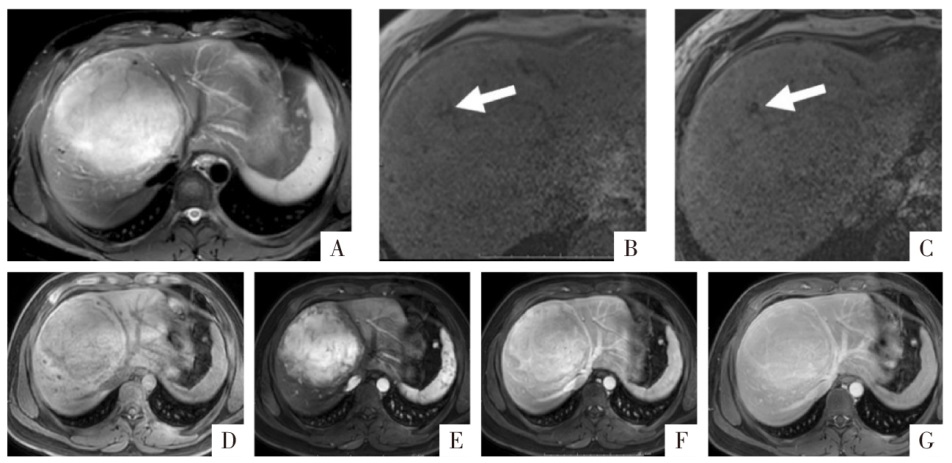

图3

脂肪组织MRI表现。病人女,50岁,上皮样血管平滑肌脂肪瘤,病灶内含有小块的脂肪组织(粗、细箭头)。A、B、C图分别为三维GRE序列T

1

WI同相位、反相位、水像(即脂肪抑制像),显示相应脂肪组织在同相位(A)为高信号,反相位(B)中心为高信号,周边环形勾边,脂肪抑制像上病灶信号减低(C)。